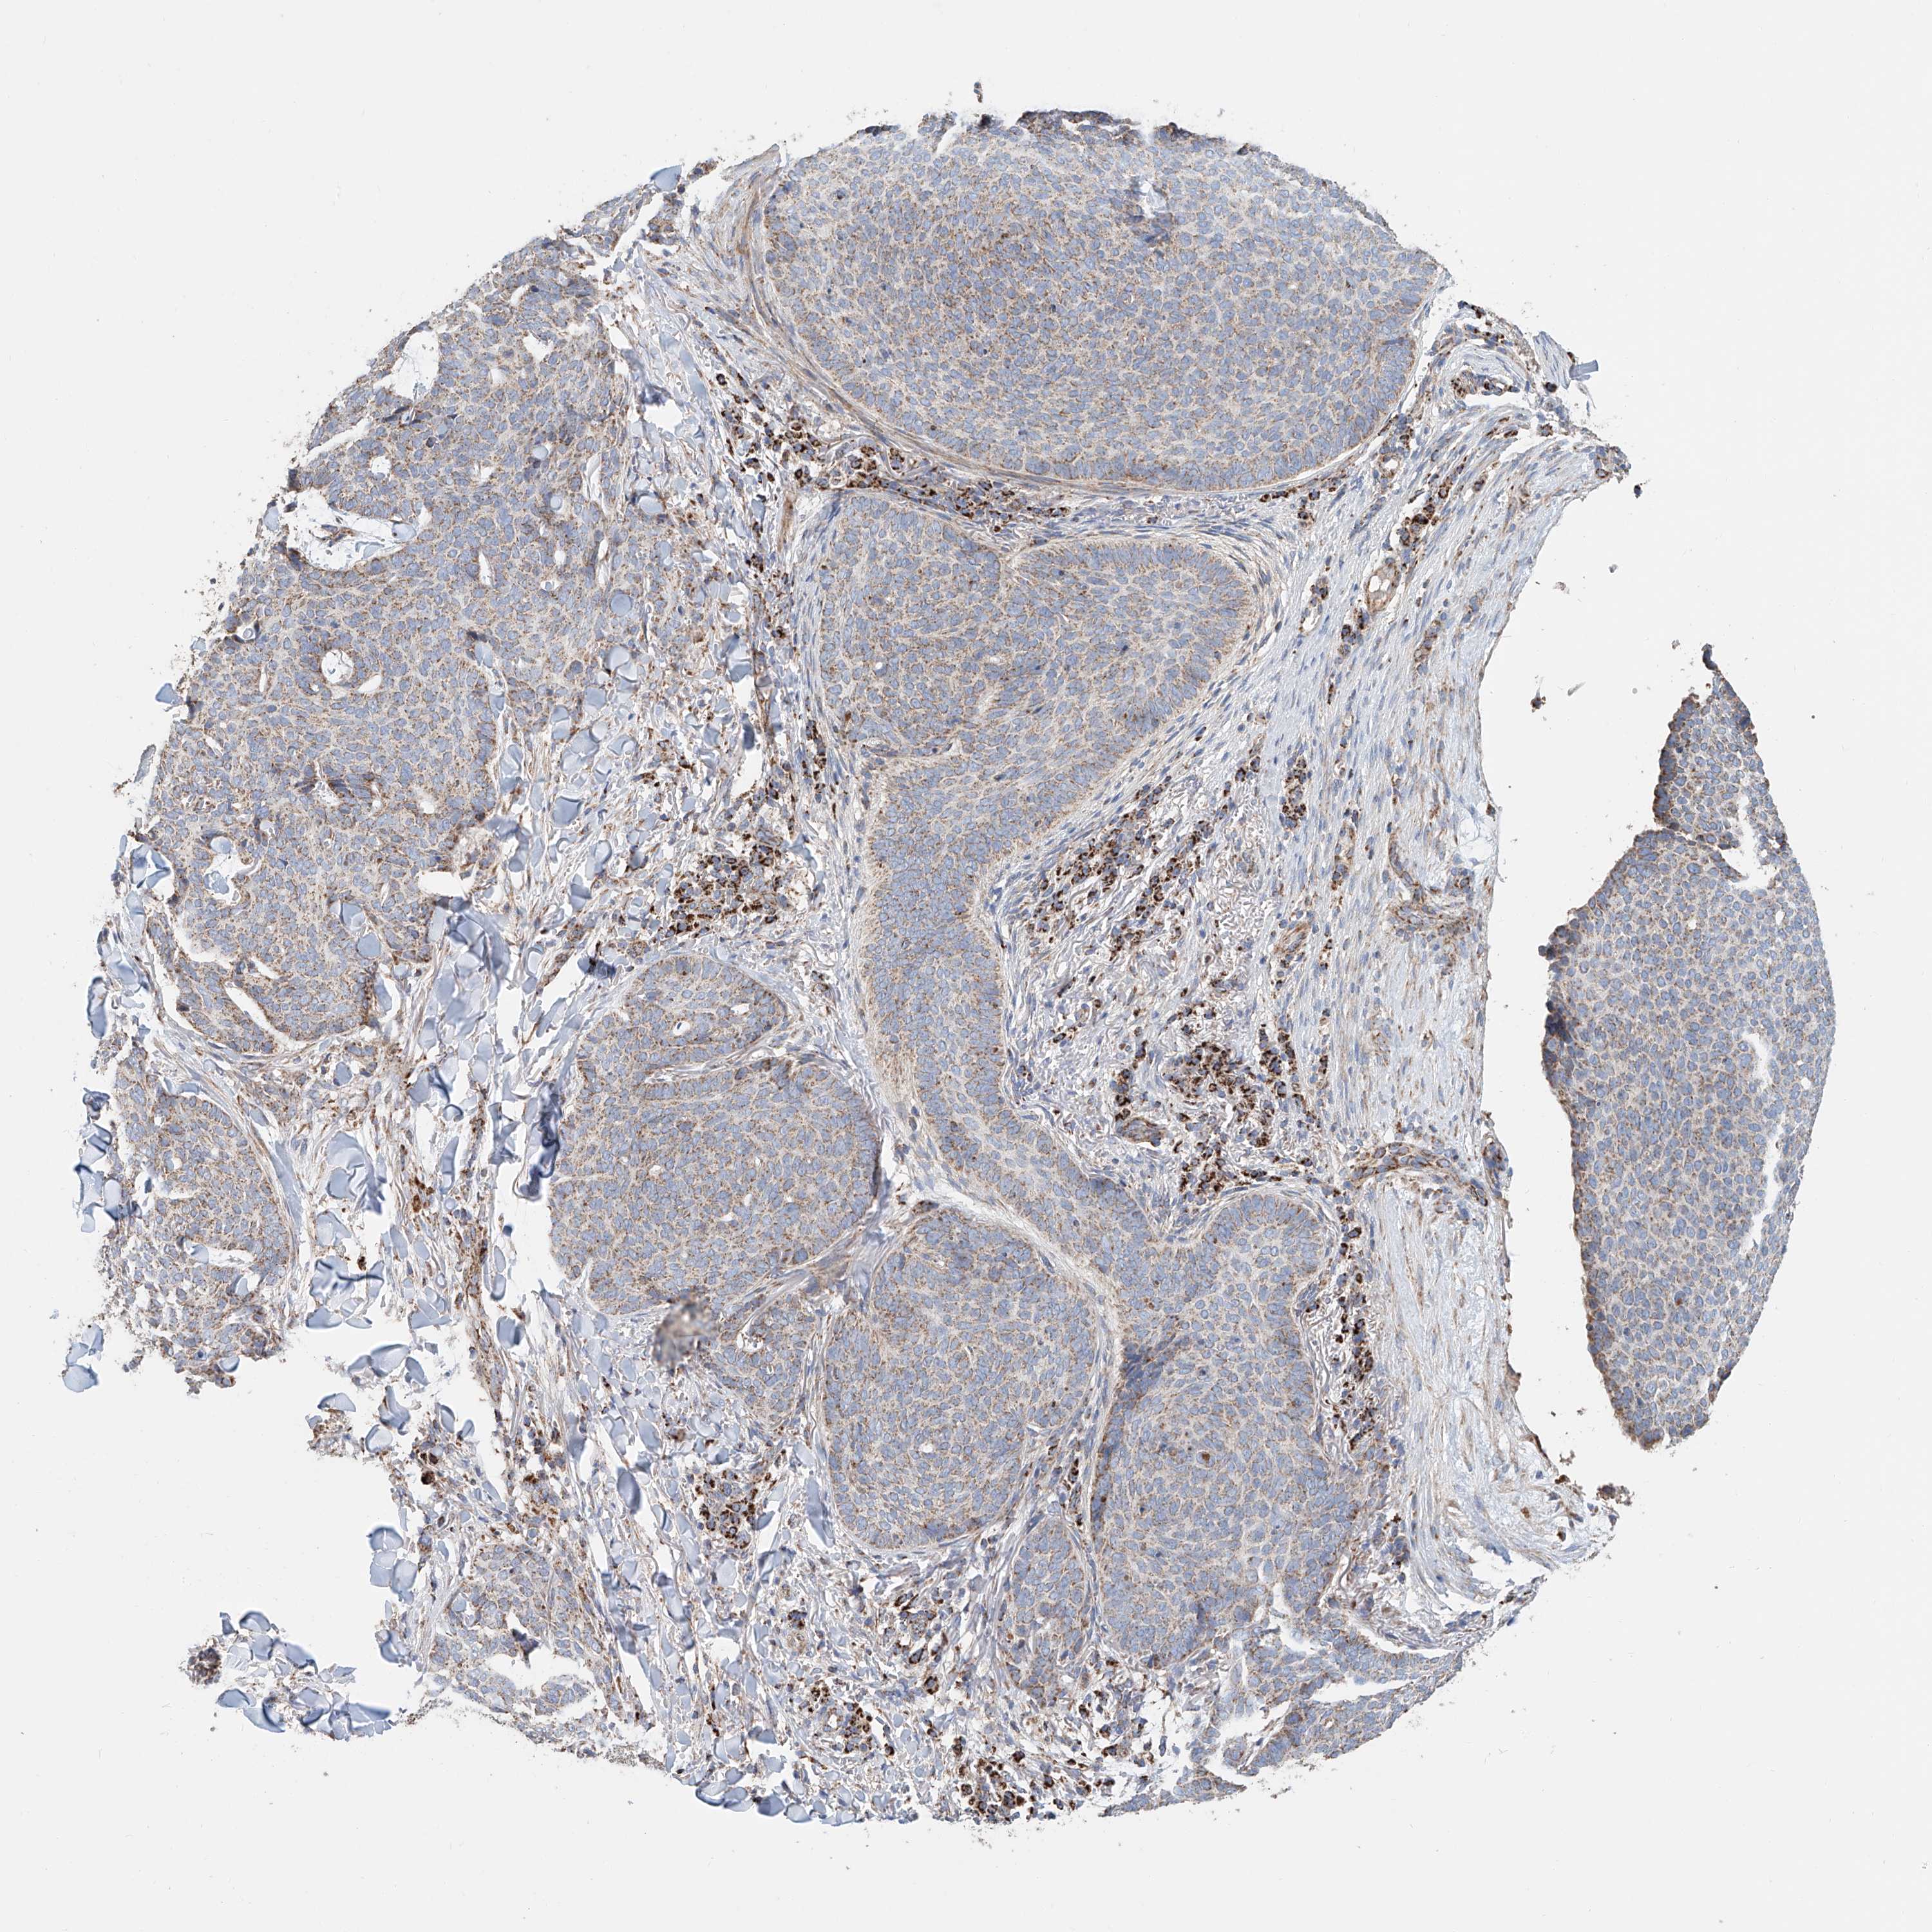

SKIN CANCER - Protein expressioni

A mouse-over function shows sample information and annotation data. Click on an image to view it in a full screen mode. Samples can be filtered based on level of antibody staining by selecting one or several of the following categories: high, medium, low and not detected. The assay and annotation is described here.

Antibody stainingi

Antibody staining in the annotated cell types in the current human tissue is reported as not detected, low, medium, or high, based on conventional immunohistochemistry profiling in selected tissues. This score is based on the combination of the staining intensity and fraction of stained cells.

Each image is clickable and will lead to virtual microscopy that enables deeper exploration of all samples and also displays staining intensity scores, fraction scores and subcellular localization as well as patient and tissue information for each sample.

Antibody CAB068195

Staining

High

Medium

Low

Not detected

Intensity

Strong

Moderate

Weak

Negative

Quantity

>75%

75%-25%

<25%

None

Location

Nuclear

Cytoplasmic/membranous

Cytoplasmic/membranous,nuclear

Squamous cell carcinoma, NOS

Squamous cell carcinoma, metastatic, NOS

Basal cell carcinoma

Papilloma, NOS